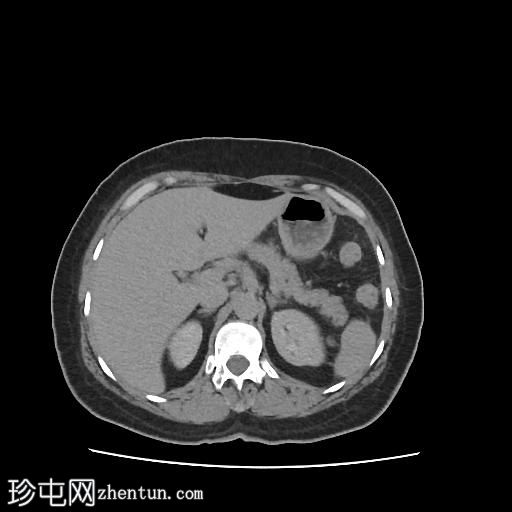

轴位增强扫描(门静脉期)

CT扫描显示:

左侧膀胱后外侧壁完全撕裂,造影剂外渗至盆腔

盆腔内可见少量积液

腹膜脂肪条索状改变,腹膜反折增厚强化,提示盆腔腹膜炎